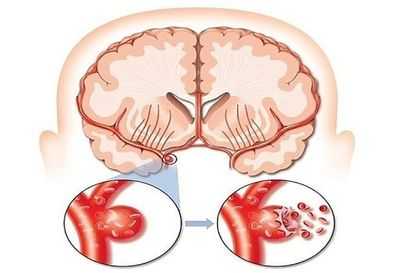

а) Патогенез. Аневризмы сосудов головного мозга возникают в местах бифуркации кровеносных сосудов. В основном они имеют мешотчатую форму, но возможны дополнительные дольки или выпячивания. Более редкое веретенообразное расширение или эктазия внутричерепных сосудов в некоторых случаях могут быть связаны с патологическими изменениями соединительной ткани или атеросклерозом. Большинство мешотчатых аневризм расположены на передней мозговой артерии (35%), затем внутренней сонной артерии (30%), и средней мозговой артерии (25%). Около 10% связаны с задним отделом артериального круга большого мозга.

1. Субарахноидальное кровоизлияние (САК). По крайней мере, 75% субарахноидальных кровоизлияний происходят в результате разрыва аневризмы. Примерно в 20% случаев идентифицировать причину не удается, а остальные имеют различные причины, в том числе артериовенозные мальформации, васкулиты и артериальные диссекции.

Классическое описание САК включает остро начинающуюся сильную головную боль, которую часто описывают, как «удар по затылку», сопровождающуюся тошнотой, ригидностью мышц шеи и светобоязнью. Около 50% пациентов теряют сознание, а в некоторых случаях развивается судорожный приступ. Потеря сознания может быть связана с внутричерепной гематомой, острой гидроцефалией или церебральной ишемией. Снижение перфузии головного мозга может произойти от внезапного резкого увеличения внутричерепного давления во время кровоизлияния и ее следует отличать от «замедленной церебральной ишемии», связанной с вазоспазмом, которая, как правило, развивается через 7-10 дней после кровоизлияния. Около трети пациентов имеют очаговую симптоматику (дисфазия и/или гемипарез), часто продолжающуюся лишь несколько часов.

е) Повторное кровоизлияние. Около 40% пациентов с аневризматическим САК перенесут повторное кровоизлияние в течение первых трех недель при отсутствии лечения. Этот риск наиболее высок в первые 24 ч после САК. После шести месяцев риск снижается до 3,5% в год, и сохраняется, по крайней мере, в течение последующих 10 лет. Только хирургическое лечение аневризмы предотвращает повторное кровотечение. Антифибринолитическая терапия не приносит никакой пользы, так как снижение риска повторного кровоизлияния сопровождается повышенным риском ишемии головного мозга.